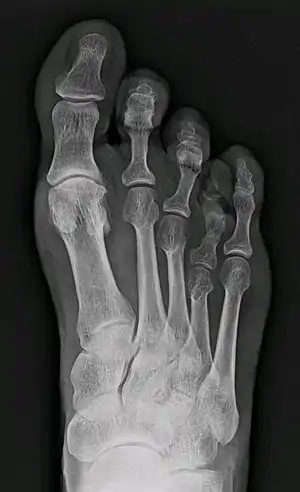

Brachymetatarsia

Brachymetatarsia is a condition in which there is one or more abnormally short or overlapping toe bones (metatarsals).[1] This condition may result due to a congenital defect or it may be an acquired condition.[1] It most frequently involves the fourth metatarsal. If it involves the first metatarsal, the condition is known as Morton's syndrome.[1] Treatment is via a number of differing surgical procedures.[1]

| X-ray of congenital brachymetatarsia involving fourth metatarsal bone | |